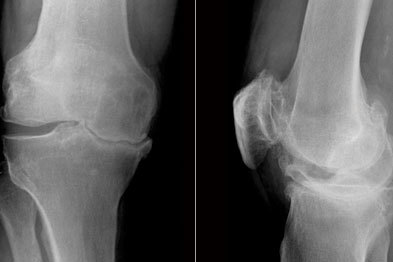

骨关节炎是一种慢性的、逐渐加重的关节老化疾病。这种病有许多不同的名称,如:退变性关节炎、增生性关节炎、肥大性关节炎、退行性骨关节病等,现在一般统称为“骨关节炎”。这种病的特点是关节软骨面发生老化、剥脱、消失,关节边缘有骨刺形成,老化的速度超过了修复和再生的速度,最后活动能力丧失。膝关节骨关节炎在临床上表现为慢性发展的关节肿痛、僵硬、活动受限,并伴有少量关节积液。这种病是最常见的关节疾病,患者数量比其他所有关节炎的总和还要多,也是关节疼痛最常见的原因之一。骨关节炎是关节软骨的老化和损伤,很多人到了40岁以后,都会出现不同程度的症状,在60岁左右有一半的人会患骨关节炎,70岁以后几乎所有的人都有不同程度的骨关节炎。随着老龄人口的增多,骨关节炎会变得更为普遍,几乎成为二十一世纪的头号疾病,越来越成为医生和社会共同关注的问题。